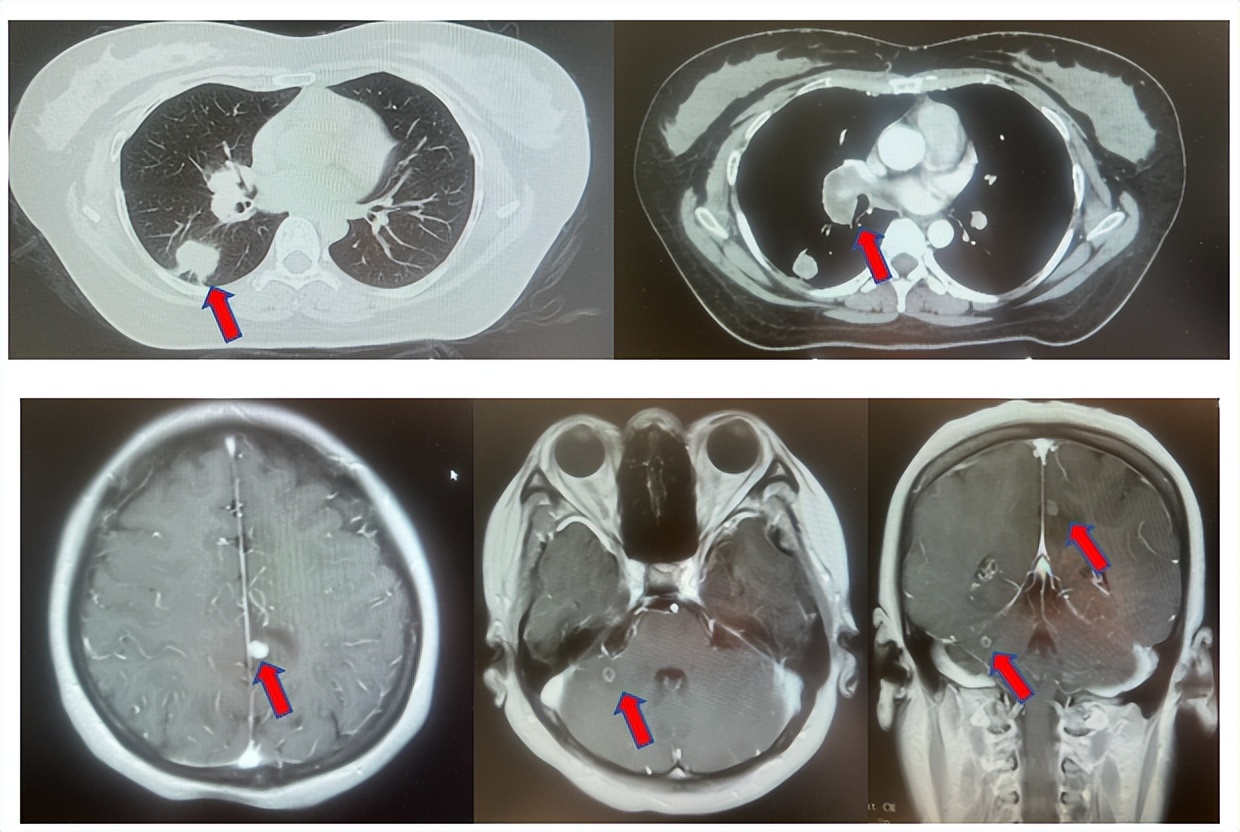

1.2影像学检查(图1)

肺+全腹CT:右肺下叶占位、伴纵隔多发淋巴结肿大,恶性可能性大;右侧心膈角结节,左侧胸廓入口淋巴结增大。

脑MRI:左侧顶叶及右侧小脑结节,转移可能性大。

图1:上两图分别展示基线肺CT肺窗及纵隔窗影像,下三图表示脑MRI影像。红色箭头指示病灶位置,分别为右肺肿物、右侧肺门转移病灶、左侧顶叶病灶、右侧小脑病灶及冠状面上的颅内两个病灶。